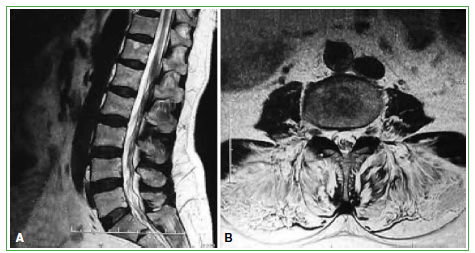

Figura 3.

Resonancia magnética anterior a la cirugía. A. En el corte sagital, no se observa patología estructural. B. En el corte axial T2, se aprecia importante sustitución grasa de la musculatura paravertebral erectora.